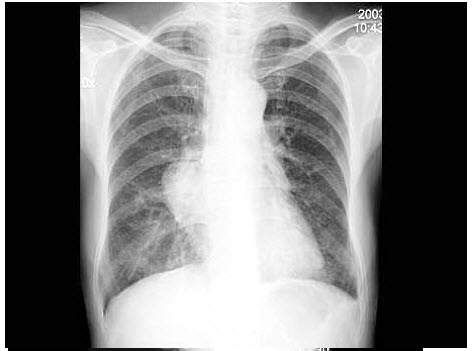

8、单项选择题

女,48岁,胸痛1周,结合图像,最可能的诊断是()

A.肺转移瘤

B.韦格肉芽肿

C.肺类风湿病

D.多发性肺脓肿

E.肺癌